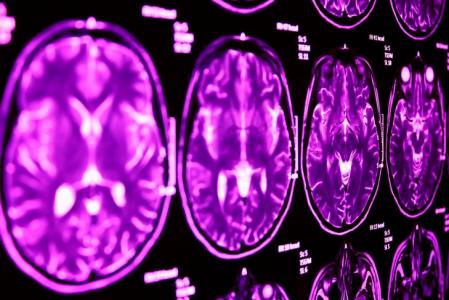

Une découverte clé : à l'aide de l'imagerie cérébrale, les neuroscientifiques montrent que la suppression du gène impacté par la suppression 2p16.3 (Neurexin1) a un impact sur la fonction des zones du cerveau impliquées dans les 2 conditions. Cette suppression génétique perturbe une zone cérébrale connue sous le nom de thalamus, et compromet sa communication avec d'autres zones cérébrales.

Ainsi, la capacité du Thalamus à communiquer avec d'autres zones est altérée par la suppression génétique.